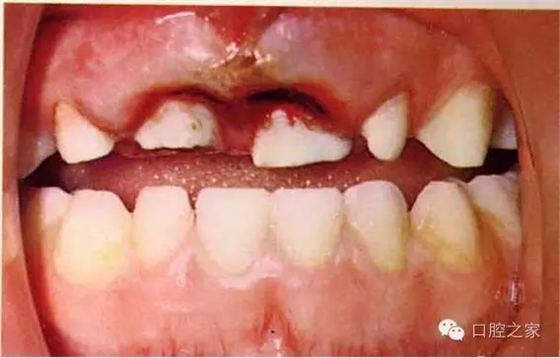

2.牙齒折斷(Tooth fracture):牙冠折斷、牙根折斷、冠根折斷

3.牙齒移位 (Displacement):牙齒挫入、牙齒側(cè)向移位、牙齒部分脫出、完全脫出(total extrusion)

2.臨床檢查:視診(缺損、色澤、移位、出血、牙齦)